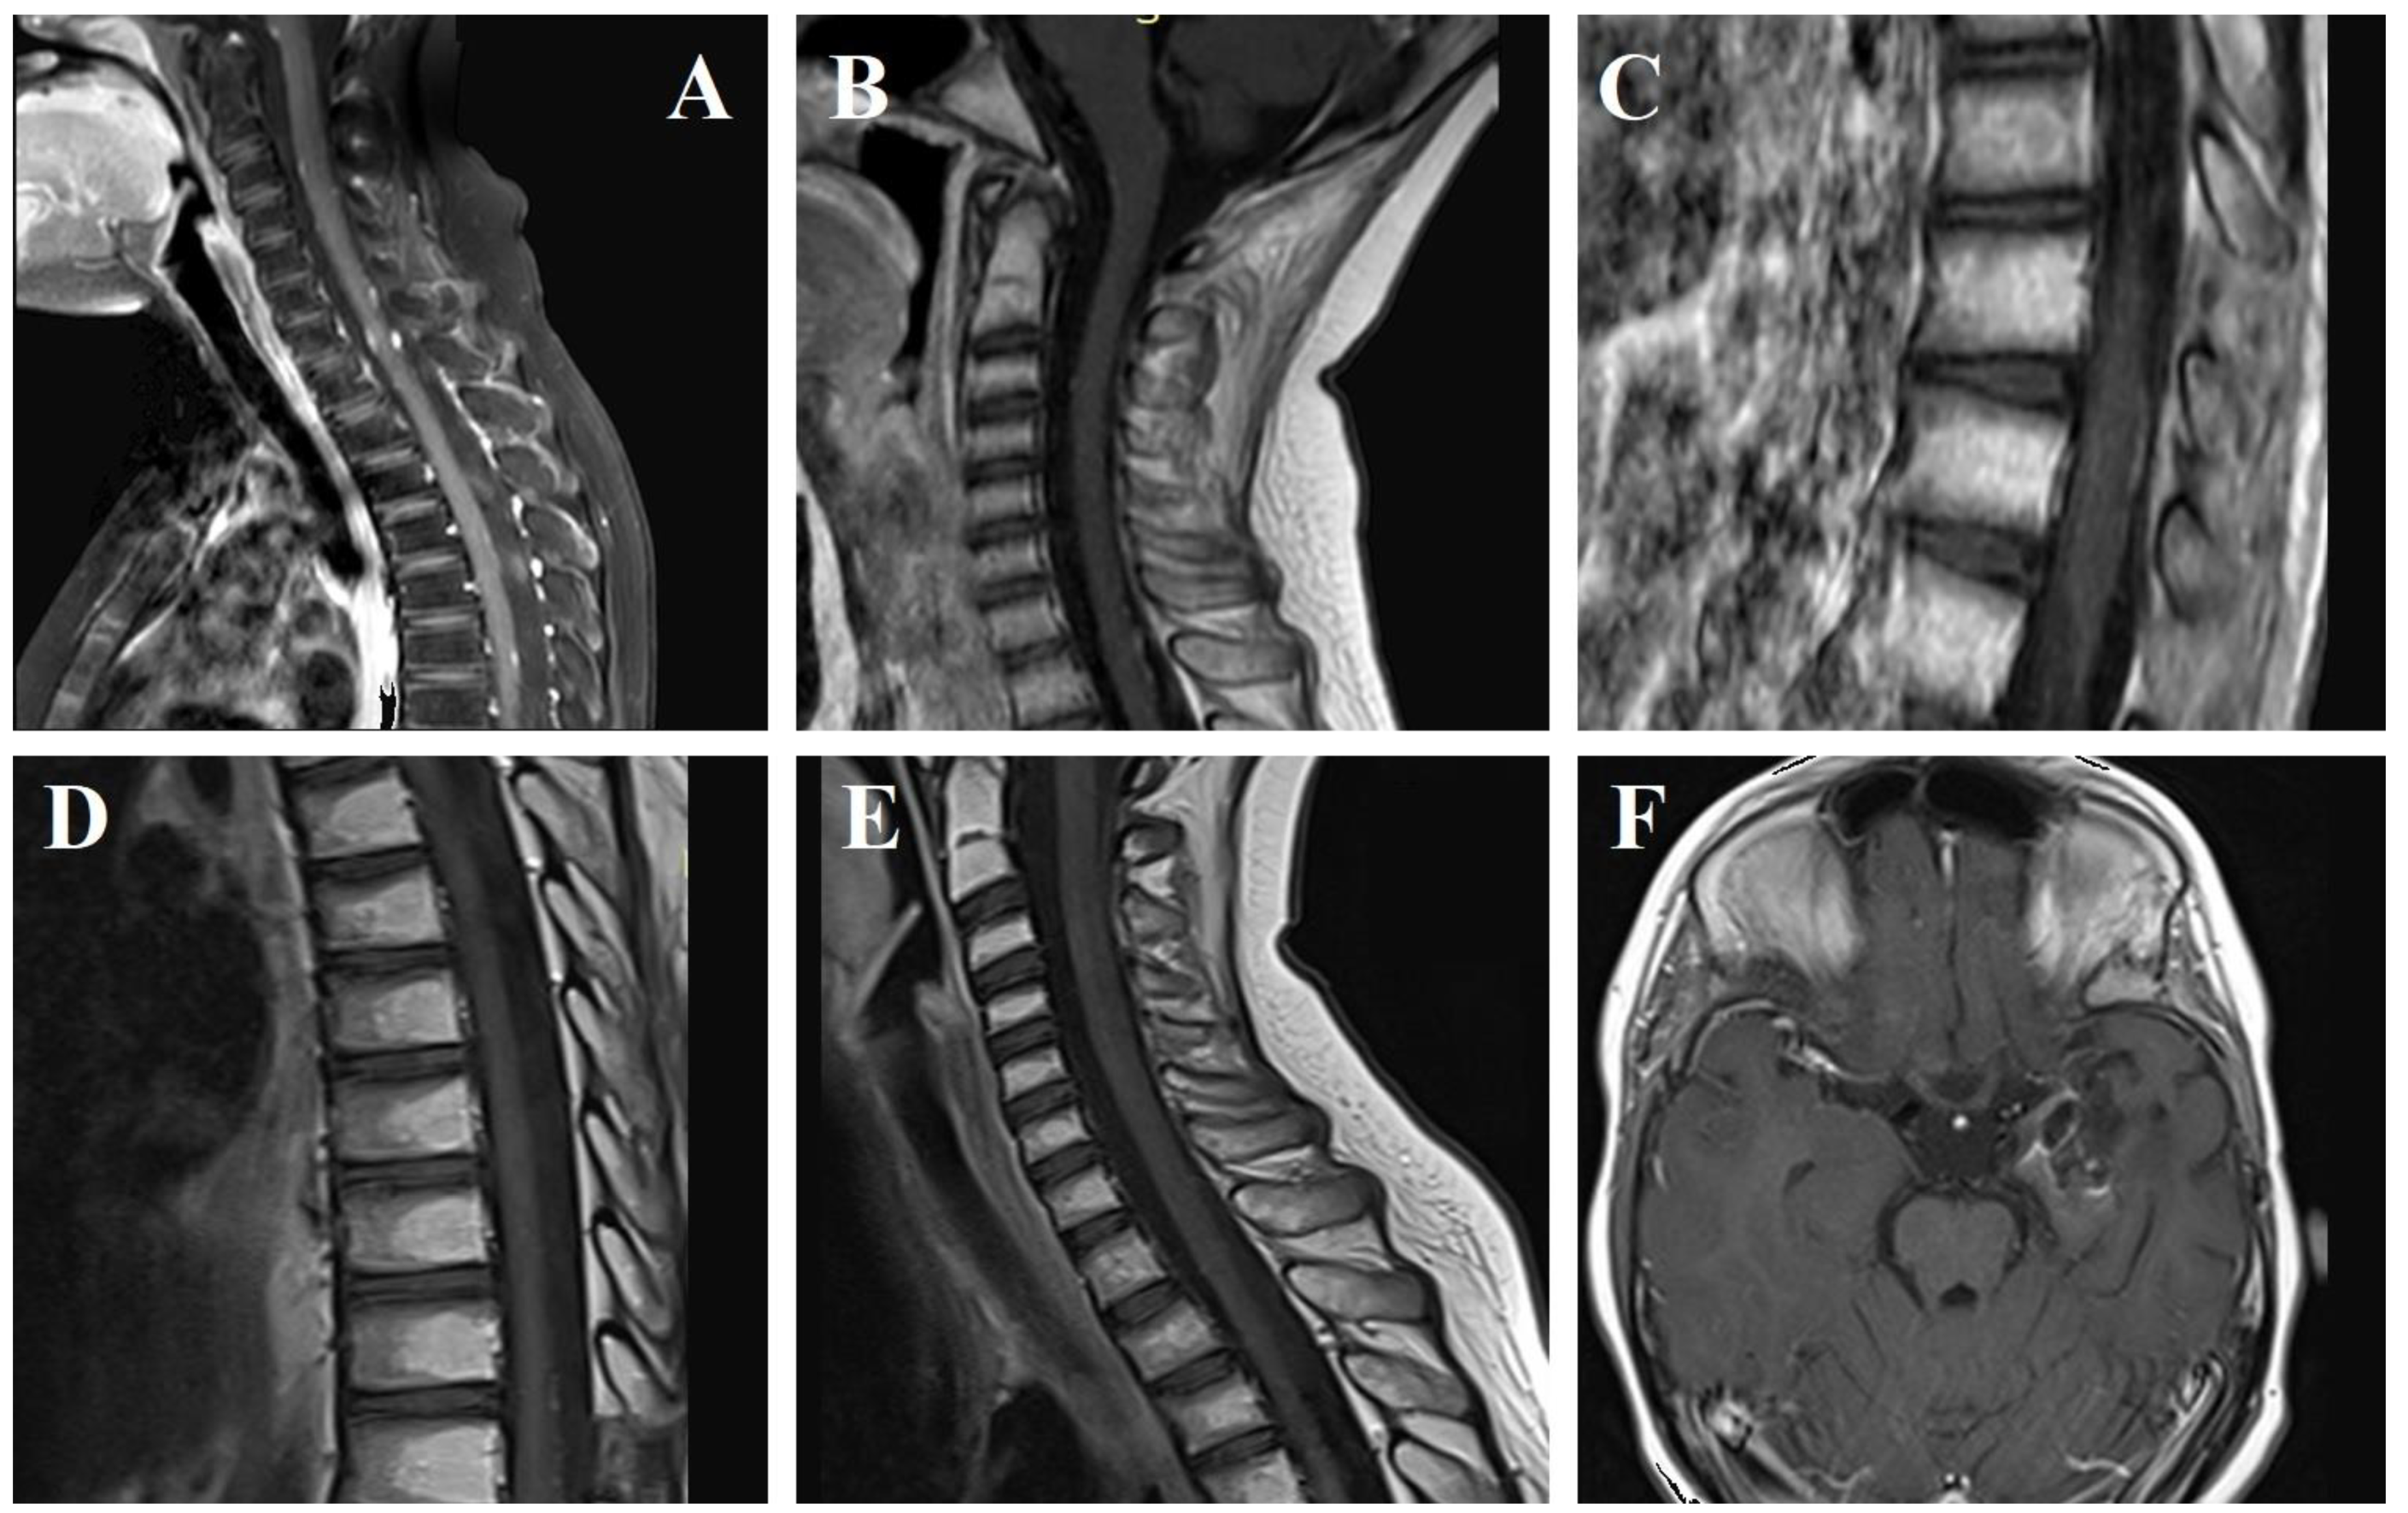

2. Case Report